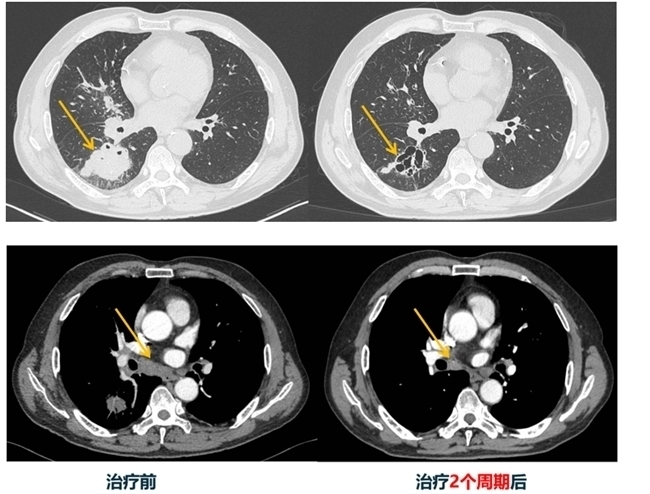

该方案创新点在于它实现了双免疫+化疗+抗血管生成的三重协同,双免疫药物负责激活患者自身免疫系统,精准识别并杀伤癌细胞;化疗直接作用于肿瘤细胞,快速抑制增殖;安罗替尼阻断肿瘤血管生成,切断其营养供应,如同多兵作战一般,三股不同的力量形成合力“围堵”肿瘤。相较于单一的免疫治疗方式,王海永主任这套方案更具前瞻性,它针对了SMARCA4缺失型肺癌的生物学特征,通过多靶点精准协同治疗的方式,突破了传统单一治疗方案响应率低、疗效不佳的瓶颈。在完成2个周期的治疗后,苗先生肺部肿瘤实性部分基本消失,转为多房空洞,最大转移淋巴结从2.3cm缩小至1.5cm,多项异常肿瘤标志物恢复正常。